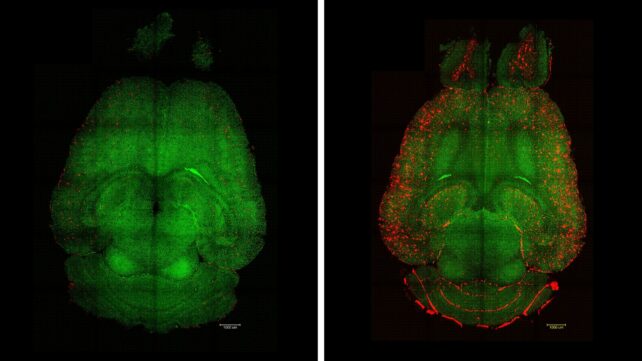

Within hours of the first injection, the animal brains showed a nearly 45 percent reduction in clumps of amyloid-beta plaques, a hallmark of Alzheimer's disease.

Using nanoparticles, not as passive carriers of medicine but as active agents of change, the researchers have altered traffic flow across the blood-brain barrier, restoring clearance of amyloid plaques in mice.